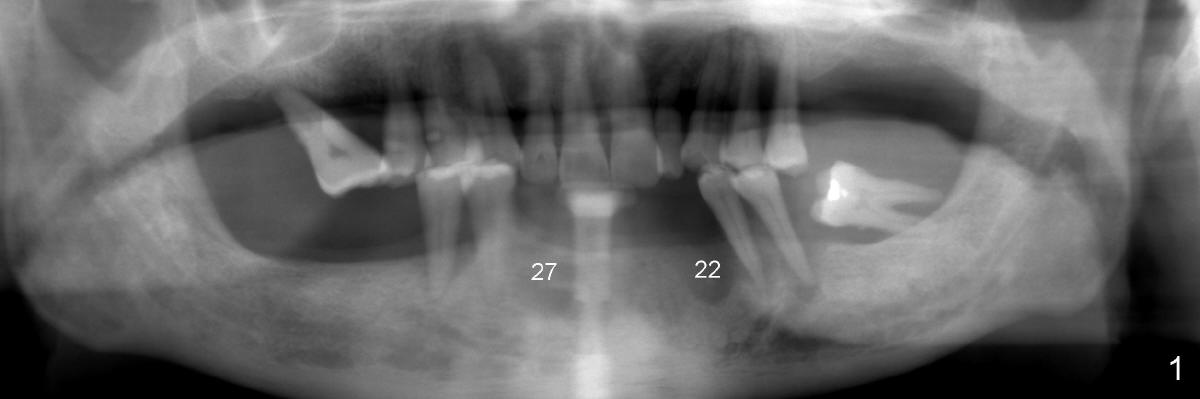

A 52-year-old man seeks treatment 2 months following loss of #22-27 fixed partial denture (FPD) (Fig.1,2).  The remaining dentition has moderate to severe chronic periodontitis.  Scaling & root planing has been done for the upper arch.  Full mouth reconstruction is planned for the lower one in two steps.  In the first procedure, the teeth #18, 20 and 21 are extracted; an incision is made from #20 to #27; two immediate implants are placed at the sites of #20,21 (one or two piece, Fig.3,5 X); another two implants at #22,27 (recently healed sites: Fig.3-5: I) and two one piece implants at lateral incisor region (I: for an implant supported FPD).  In case one of the lower left premolars cannot have an implant due to proximity to the nerve, a FPD can be fabricated in the canine/premolar sextant. A splinted immediate provisional restoration will be fabricated from #20-27 immediately.